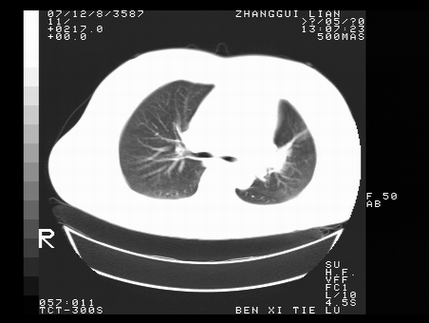

标题: CT10818:男,73,TB病史,现病史肺炎及直肠CANCER术后 [打印本页]

标题: CT10818:男,73,TB病史,现病史肺炎及直肠CANCER术后

左侧中央型肺癌伴阻塞性肺炎\\不张,左侧前上纵隔亦增宽,建议上传纵隔窗除外淋巴结转移.

考虑:左侧中央型肺癌伴阻塞性肺炎,纵隔淋巴结转移。

1)考虑为:左侧中央型肺癌伴阻塞性肺炎,纵隔淋巴结转移。2)双侧少量胸腔积液。3)心包积液。

左侧中央型肺癌伴阻塞性肺炎,纵隔淋巴结转移。

考虑左侧中央型肺癌伴阻塞性肺炎,纵隔淋巴结转移。